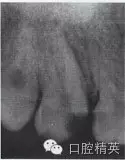

患牙根管的數(shù)目、位置以及根管的彎曲度和彎曲方向,也是影響外形制備的重要因素。為了使根管預(yù)備器械在無干擾的情況下進(jìn)入每一個根管,洞壁經(jīng)常被延長,入口的外形就隨之發(fā)生改變(圖4-2、3)。

圖4-2 洞壁被延長

A.術(shù)前X線片

B.洞壁被延長

C.根充及全冠修復(fù)

圖4-3 延長洞壁的病例